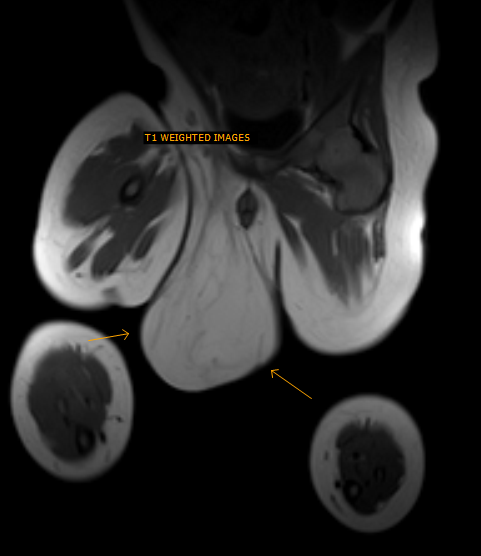

Scrotal Lipoma-MRI – Sumer’s Radiology Blog